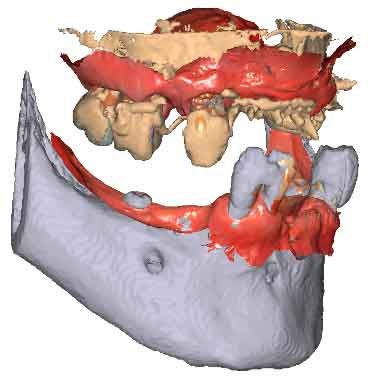

Lorsque les scans IOS traditionnels manquent de références nécessaires, les données du CBCT peuvent servir d'alternative viable. En utilisant les fichiers du CBCT, le clinicien peut établir des références anatomiques précises pour la planification du traitement.

Pour pouvoir utiliser les données CBCT comme modèles initiaux, nous devons transformer le fichier DICOM en un fichier STL. Découvrez-en plus sur la segmentation CBCT et son utilisation dans TWIM ci-dessous.

En important les fichiers DICOM du patient au lieu des scans IOS, les cliniciens peuvent enregistrer le mouvement de la mâchoire, facilitant ainsi la planification précise du traitement.

Importez les modèles CBCT segmentés en tant que modèles initiaux dans TWIM

Sélectionnez 4 points virtuels sur la mandibule du modèle osseux importé